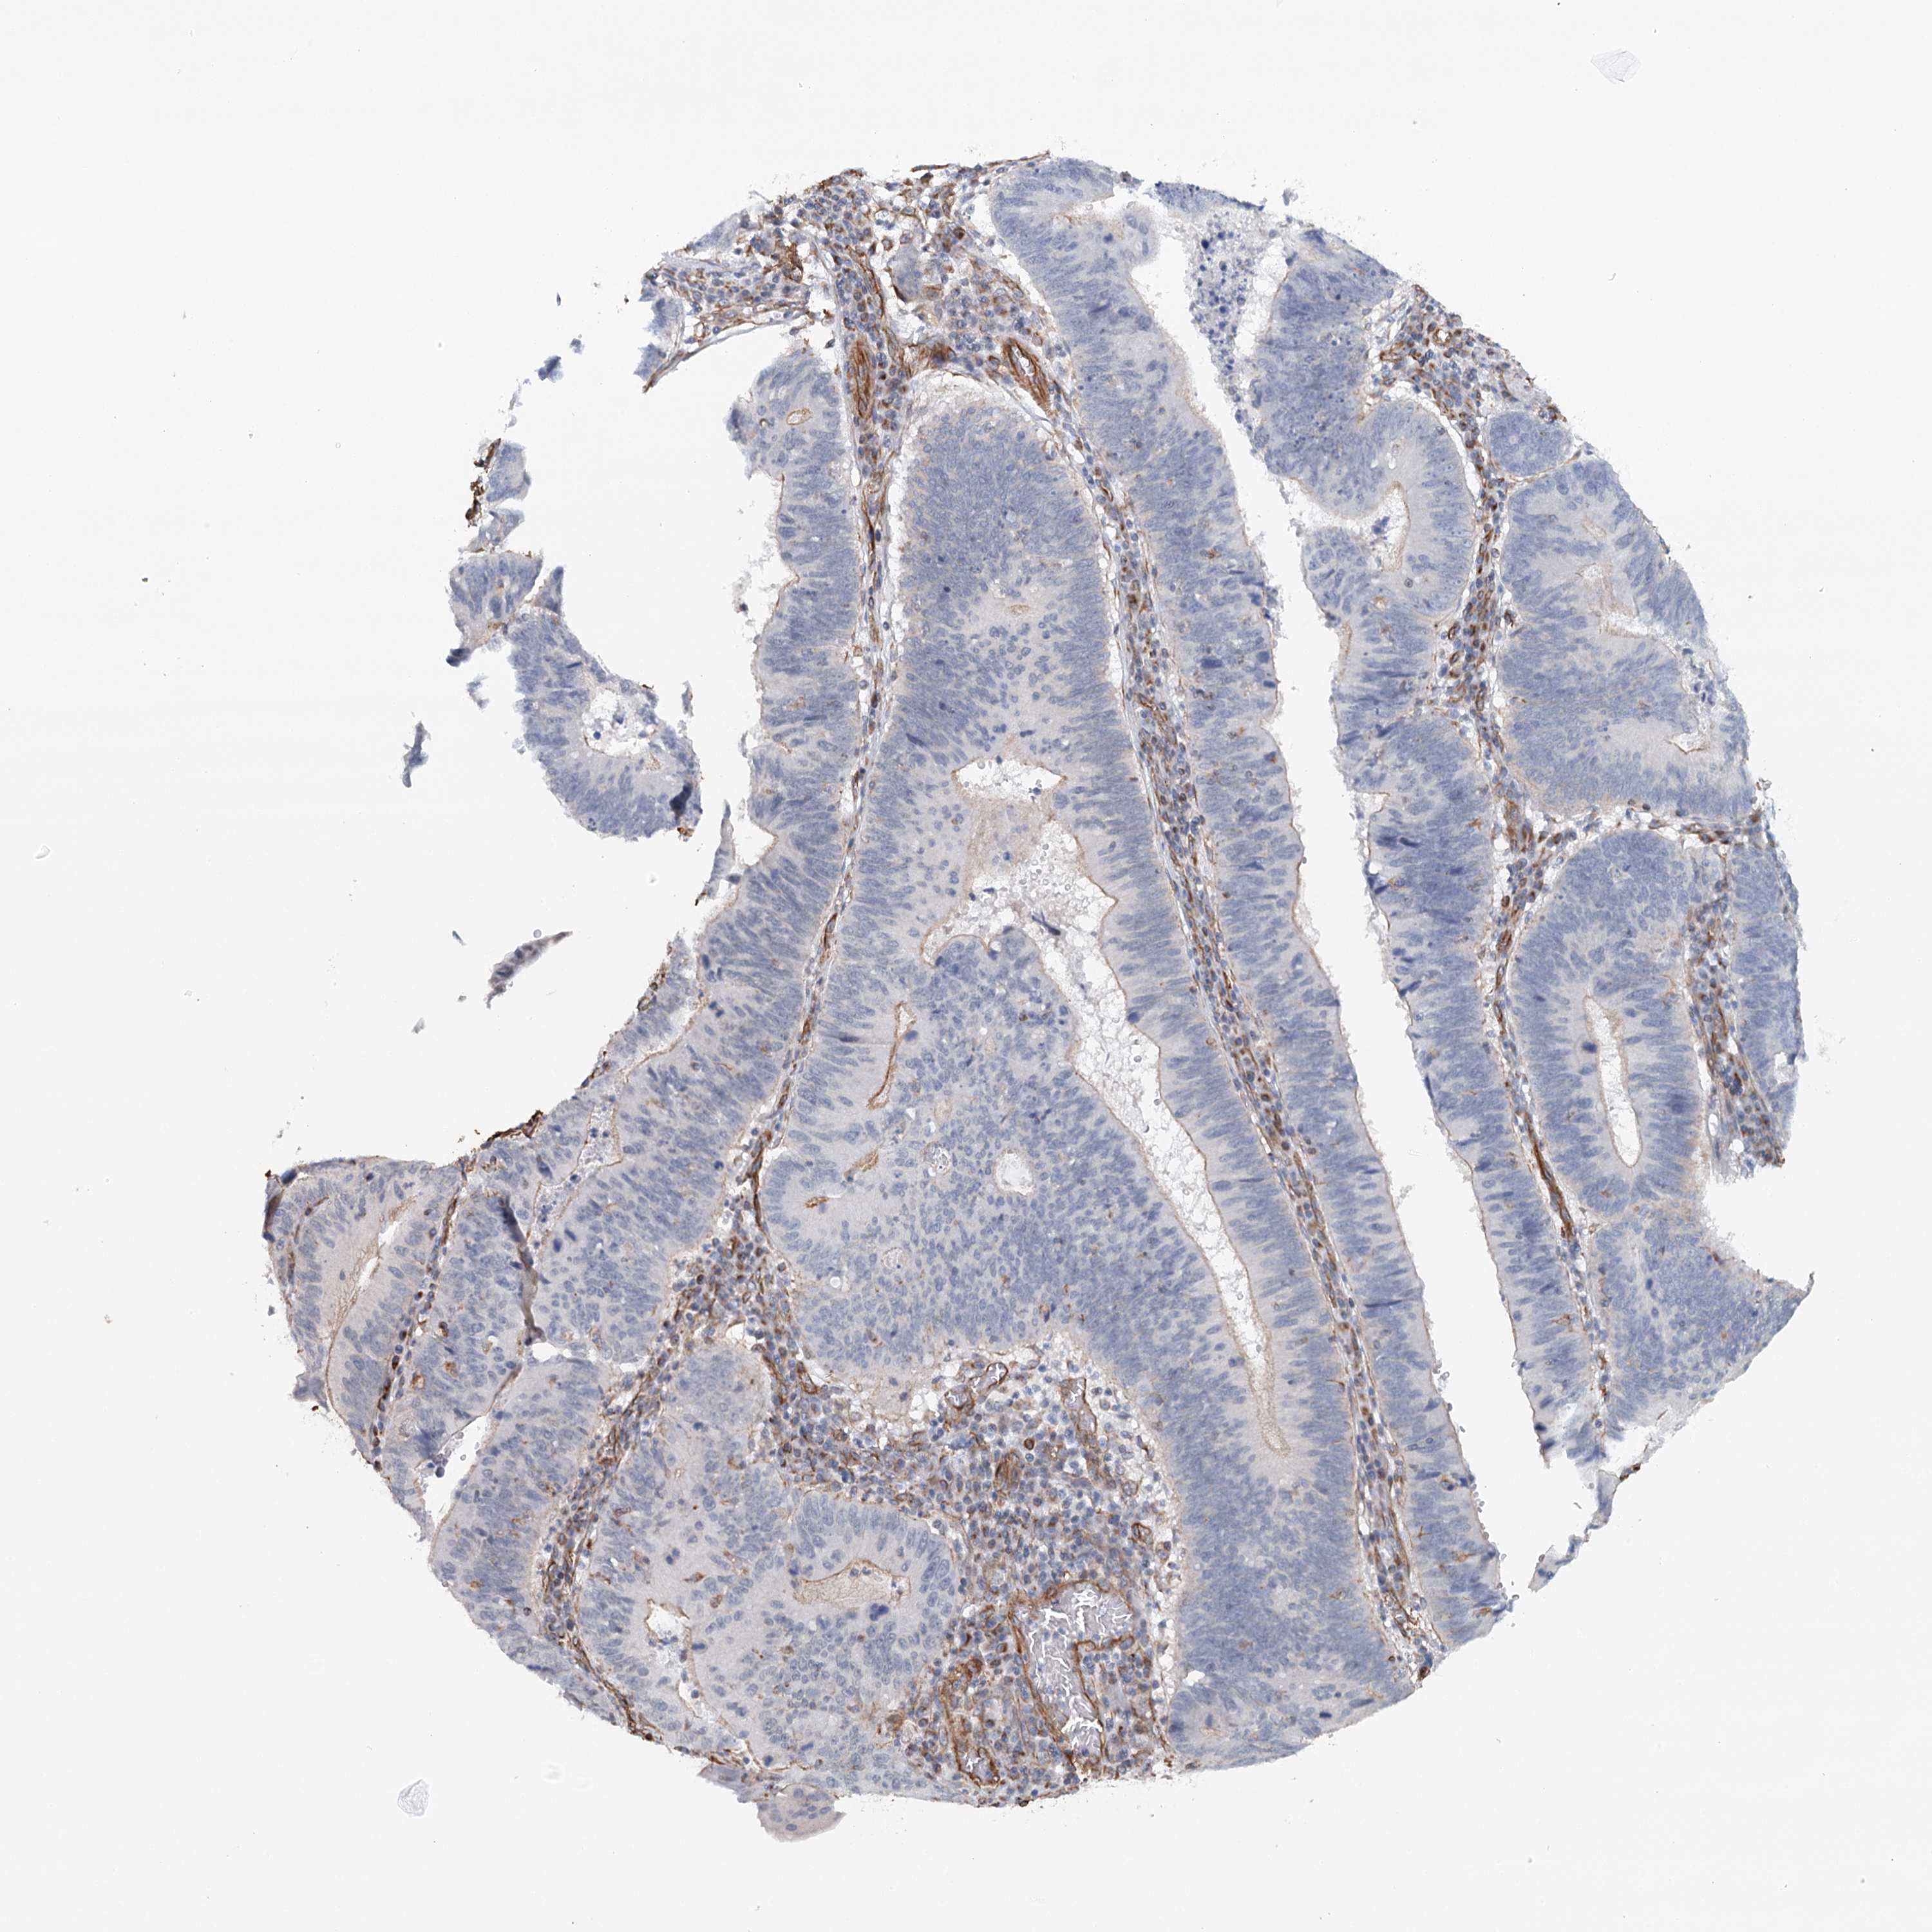

STOMACH CANCER - Protein expressioni

A mouse-over function shows sample information and annotation data. Click on an image to view it in a full screen mode. Samples can be filtered based on level of antibody staining by selecting one or several of the following categories: high, medium, low and not detected. The assay and annotation is described here.

Note that samples used for immunohistochemistry by the Human Protein Atlas do not correspond to samples in the TCGA dataset.

Antibody stainingi

Antibody staining in the annotated cell types in the current human tissue is reported as not detected, low, medium, or high, based on conventional immunohistochemistry profiling in selected tissues. This score is based on the combination of the staining intensity and fraction of stained cells.

Each image is clickable and will lead to virtual microscopy that enables deeper exploration of all samples and also displays staining intensity scores, fraction scores and subcellular localization as well as patient and tissue information for each sample.

Antibody HPA034631

Antibody HPA071347

Antibody CAB033265

Antibody CAB037325

Staining

High

Medium

Low

Not detected

Intensity

Strong

Moderate

Weak

Negative

Quantity

>75%

75%-25%

<25%

None

Location

Nuclear

Cytoplasmic/membranous

Cytoplasmic/membranous,nuclear

Adenocarcinoma, NOS

Adenocarcinoma, High grade